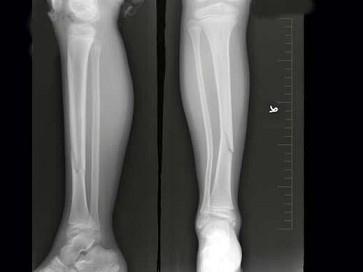

问题 女,8岁,外伤后致右胫骨骨折,如图所示,下列描述正确的是?(?)

选项 A.对位好,对线差 B.对位差,对线好 C.对位对线好 D.对位对线差 E.以上均不正确

答案 A